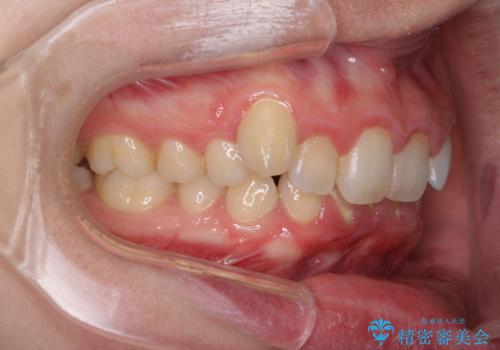

- 八重歯を気にして来院された患者様です。

八重歯の後ろの歯を1歯抜歯し、補助装置(リンガルアーチ)を用いて八重歯の位置を改善し、その後インビザラインにより矯正治療を行うこととしました。

下顎前歯が1本欠損したスリーインサイザーという状態であるため、上下の前歯の咬み込みが深くなったり、奥歯の咬み合わせが理想的なものとならなかったりという仕上がりになってしまいます。

前歯の見た目や奥歯の咬み合わせに、患者様が違和感を感じない状態として治療を終えました。